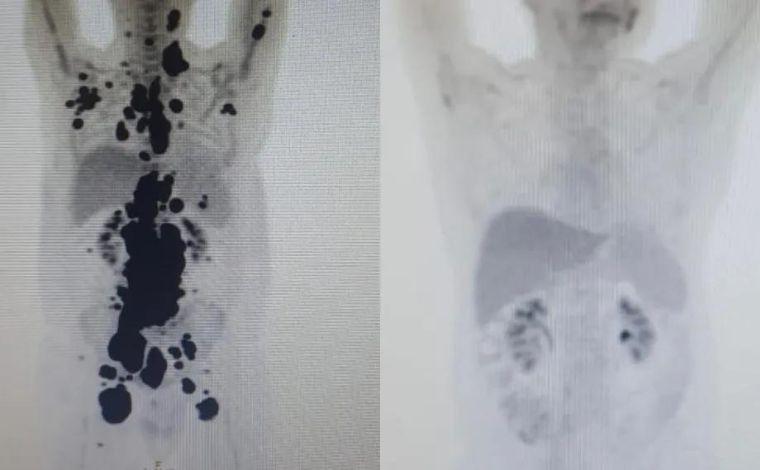

"O que foi extremamente animador é que vimos uma resposta positiva em apenas um mês em um paciente que já chegou muito debilitado no centro, com o câncer bem avançado, queixa de dor intensa e baixo índice de plaquetas, indicando que estava com a saúde bem afetada", explica o hematologista Vanderson Rocha, professor de terapia celular na Faculdade de Medicina da USP e coordenador nacional de terapia celular da Rede D'Or. Ele cuidou do caso de Peregrino no centro.

"É preciso acompanhar agora por um período de até cinco anos para confirmar se houve a 'cura' do câncer, mas, em estudos desenvolvidos nos Estados Unidos, em torno de 50% dos pacientes de linfoma são curados com CAR-T", disse.